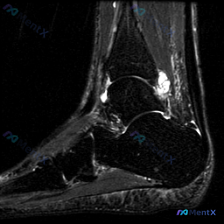

这是一份踝关节矢状位T2加权像(T2WI),先给大家说下客观观察到的结果:

- 解剖结构显示清晰:可以看到胫骨远端、距骨、跟骨、足舟骨及部分跖骨

- 核心异常发现:

- 胫距关节腔前方、后方可见明显T2高信号,提示大量关节腔积液

- 踝关节前方、尤其是后踝区域,可见边界清晰的结节状/团块状T2高信号影,位于关节囊内或关节囊周围

- 踝关节前方及后方软组织可见轻度非弥漫性肿胀

- 阴性发现(排除常见问题):

- 所有显示骨质未见弥漫性骨髓水肿,骨皮质信号正常,没有明确骨折线、骨塌陷,也没有明显应力性骨折表现

- 关节对位正常,没有脱位

- 距骨穹窿关节软骨未见明显缺损剥脱

- 胫骨前缘和距骨颈部没有明显巨大骨赘

- 跟腱走行连续,信号正常,可见部分肌腱没有明显严重断裂征象

拿到这份影像第一眼看到大量T2高信号,很容易直接诊断为「软组织积液」,但仔细看会发现不对——单纯积液应该是弥漫性液体信号,而这里有明确的结节状团块,所以思路得调整,核心问题是「踝关节内/周围占位性病变伴积液」,不是单纯外伤性积液。